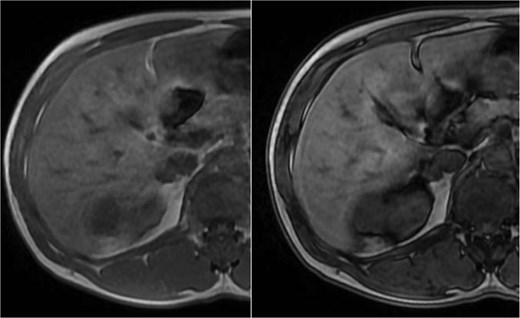

Abdominal magnetic resonance imaging (MRI) showed approximately seven to eight right renal masses (largest 32 × 35 × 37 mm) and five to six left renal masses (largest 62 × 55 × 55 mm). The renal lesions were iso- to mildly hypointense on T1-weighted imaging and mildly hypointense on T2-weighted imaging, without macroscopic fat. Post-gadolinium images demonstrated heterogeneous enhancement with central necrosis in the dominant masses (Fig. 3). Diffusion-weighted imaging showed marked restriction in the viable tumor components (Fig. 4). The dominant left renal mass, located in the mid kidney, demonstrated invasion of the posterior renal fascia. Subacute hemorrhage under the left renal capsule measured up to 24 mm in thickness.

Axial T1-weighted and T2-weighted MRI showing multiple solid renal masses with low signal intensity and a large left subcapsular hematoma.